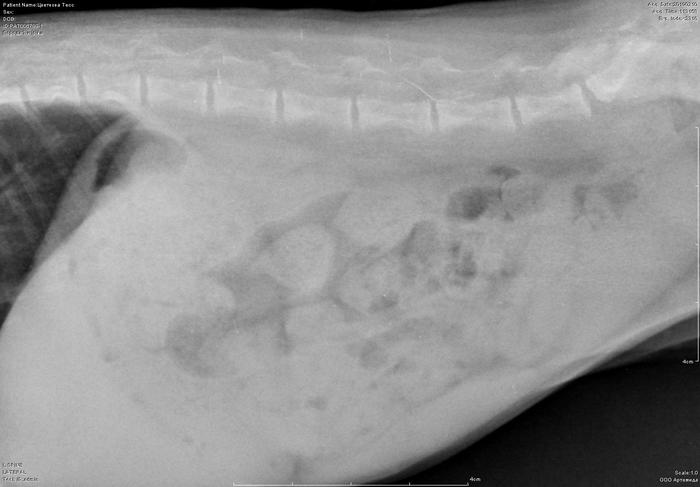

Рентген котенка

Добрый день. Котенок рожден 5 ноября 2018 года, девочка, не привита. Проглистована. Неожиданно в один момент стала припадать на задние ноги. Как бы бережет их и старается не прыгать лишний раз. Свозили два дня назад к ветеринару - всю её прощупал, говорит переломов нет, вывихов тоже. Сделали блокаду ближе в крестцу новокаина, чтобы снять симптомы. Прописал кальций в таблетках Ексел. Сейчас всё примерно так же - лапки задние бережет, но стала по активнее. Прошу специалистов, если такие тут бывают, оценить снимки, т.к. врач ещё кое-что сказал и хотелось бы услышать ваше мнение. Скан расшифровки и д/з потом приложу.

Фронтальная проекция